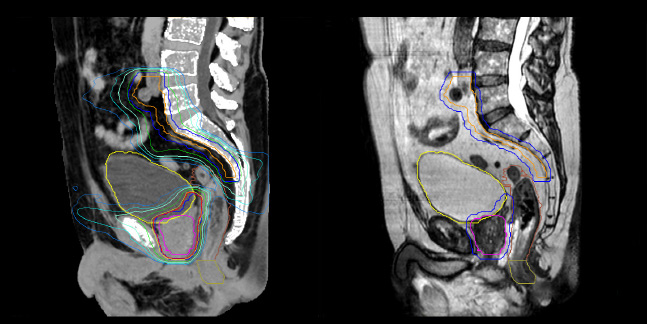

Dr. Champion appreciates that MRCAT Pelvis also enables rectal cancer simulation in the prone position, allowing the digestive anatomy to be moved away from the treatment volume by projecting them forward.

“The irradiation volumes for a rectal cancer are essentially posterior and lateral, so good sparing of the digestive structures improves tolerance of the treatment,” he says. “Prone positioning can also be applied to anal cancer simulation. This position enables the gluteal muscles to be moved apart, which significantly reduces the toxicity associated with radiation concentrating in the folds.”

MRCAT Pelvis also allows an up to 36-centimeter FOV in the feet-head direction, permitting creation of treatment plans covering extended pelvic targets.

“The large field-of-view is definitely useful and a must-have functionality,” Dr. Champion observes. “For several patients, we have treated the lymph nodes where the radiation fields are longer than 30 centimeters. In our practice, contouring of the pelvic lymph node areas is indicated in prostate cancers of intermediate or high risk. Rectal and anal canal cancer are also irradiated in the lymph node drainage areas. The cranial limit of this elective lymph node irradiation extends up to the aortic bifurcation, which often corresponds to the L4-L5 vertebral disc.”